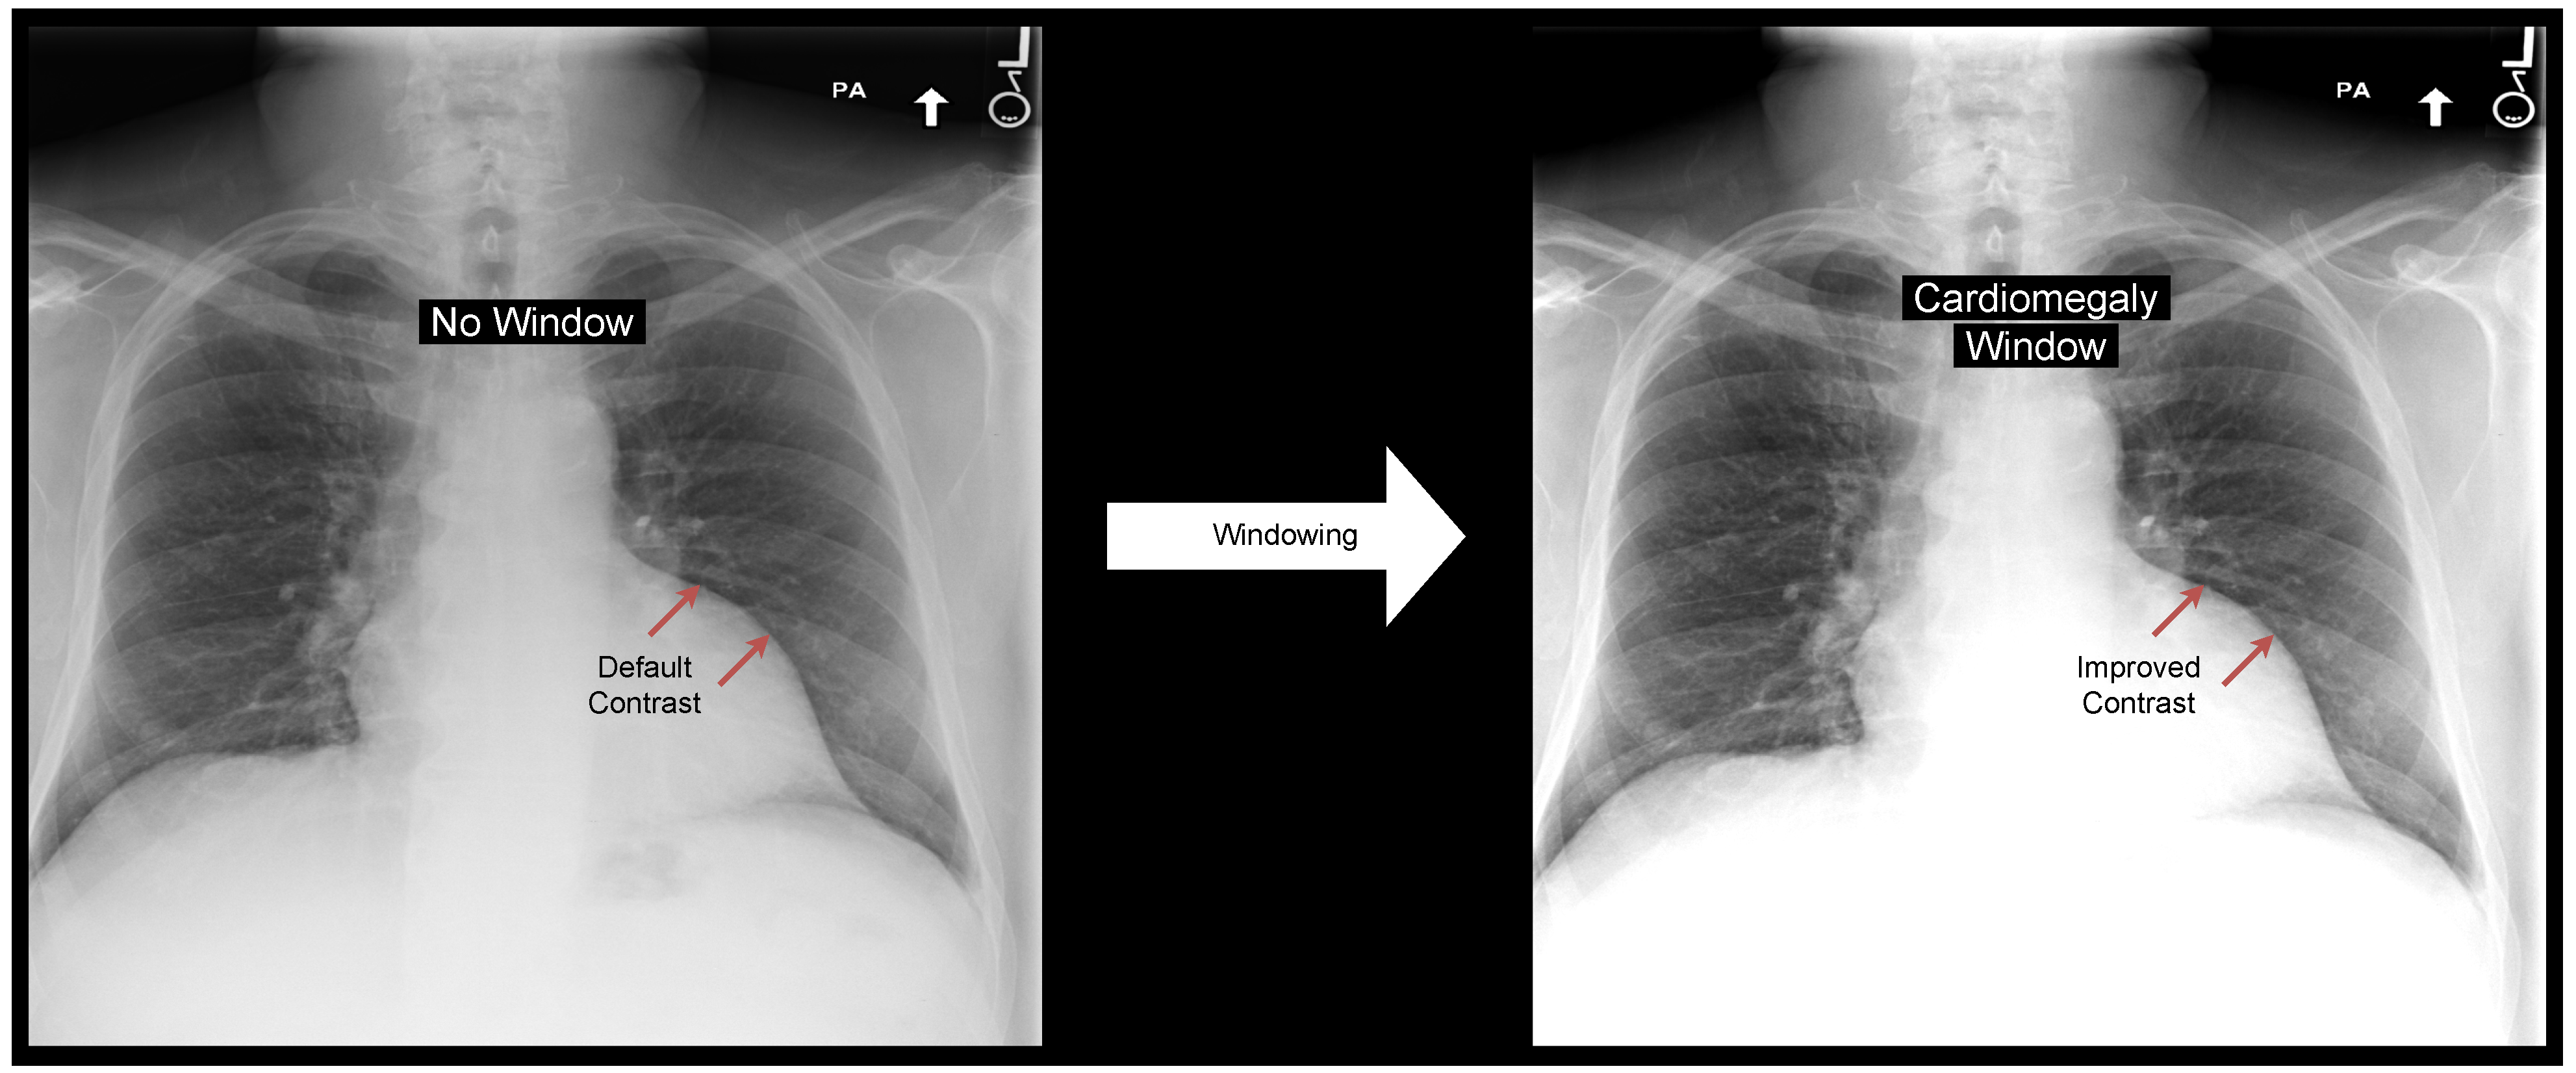

- We demonstrate that applying a window to chest radiographs as a pre-processing step increases classification performance.

2.4. Windowing